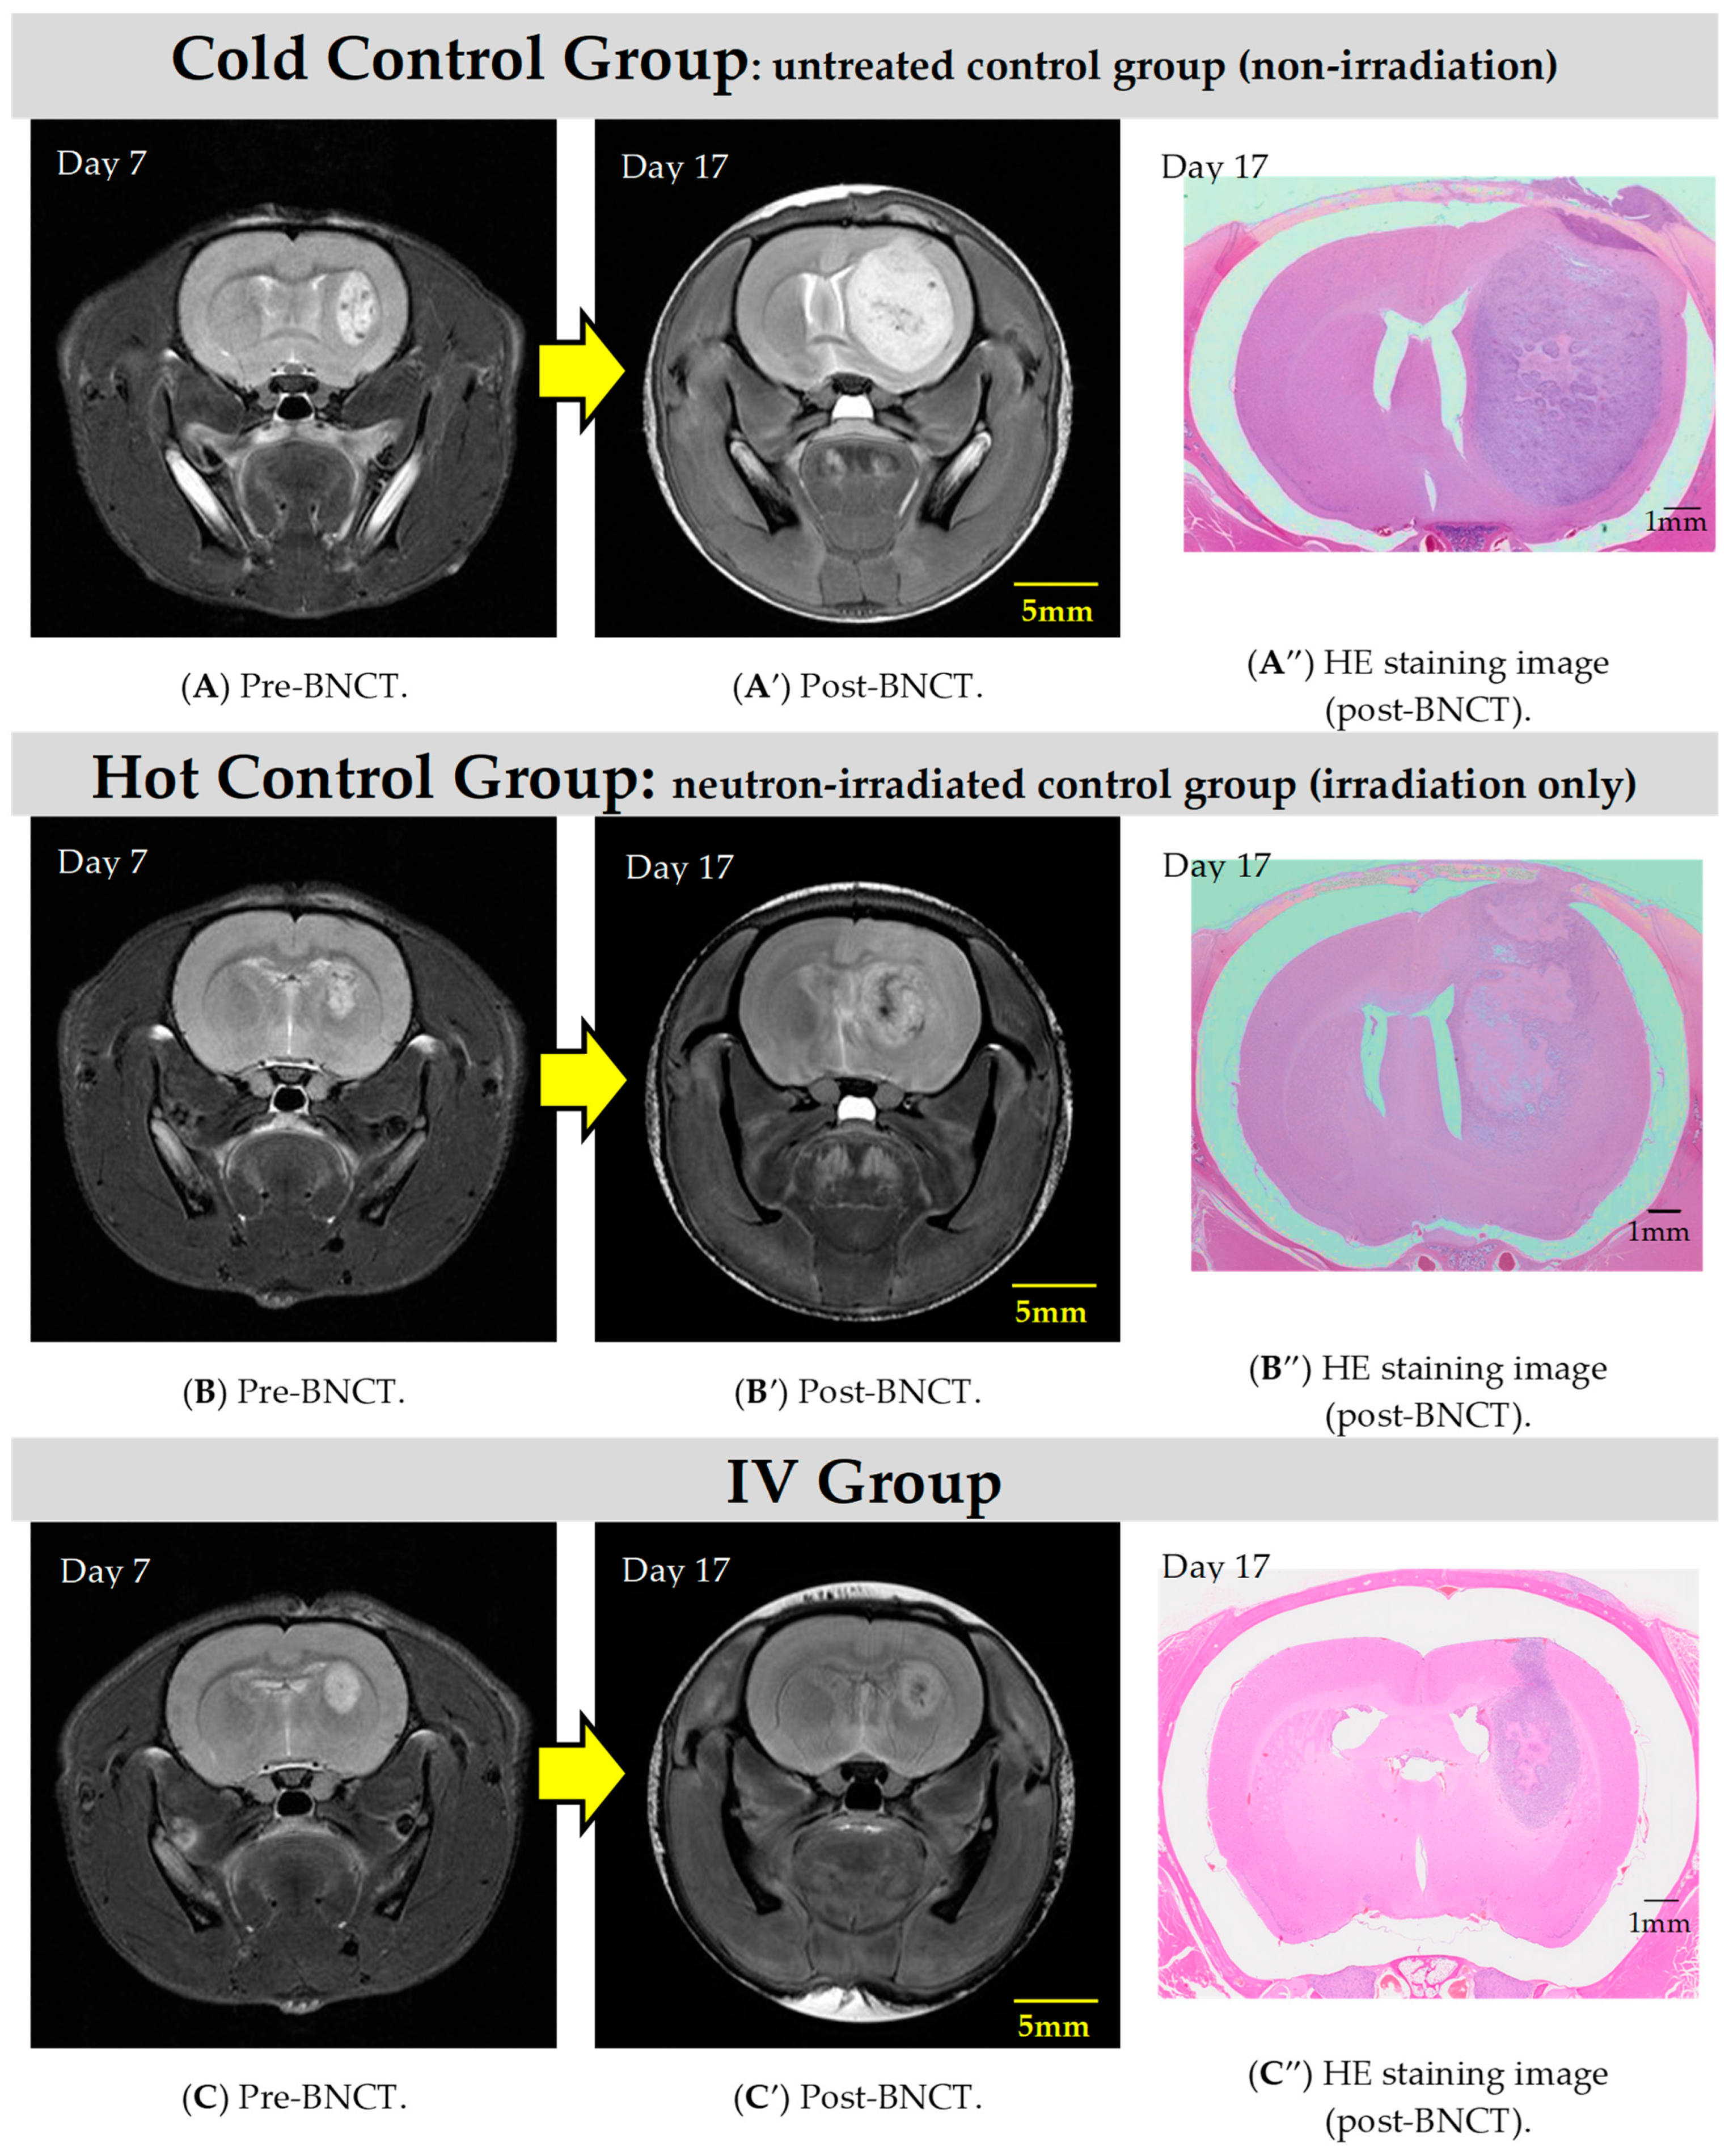

2.2. BNCT Effect on the CSF Administration Method of 10BPA

2.3. Pre- and Post-Treatment MRI Assessment

2.4. Hematoxylin and Eosin Staining of C6 Rat Glioma Brain Sections

| Day 0 * | Day 7 | Day 10 | Day 17 | |||

|---|---|---|---|---|---|---|

| C6 Cell Transplantation | MRI (Pre-BNCT) | BNCT | MRI (Post-BNCT) | HE Staining | ||

| BPA | Irradiation | |||||

| Cold control group ** | ◯ | A | - | - | A′ | A″ |

| Hot control group *** | 〇 | B | - | 20 min | B′ | B″ |

| IV group | 〇 | C | 350 mg/kg | 20 min | C′ | C″ |